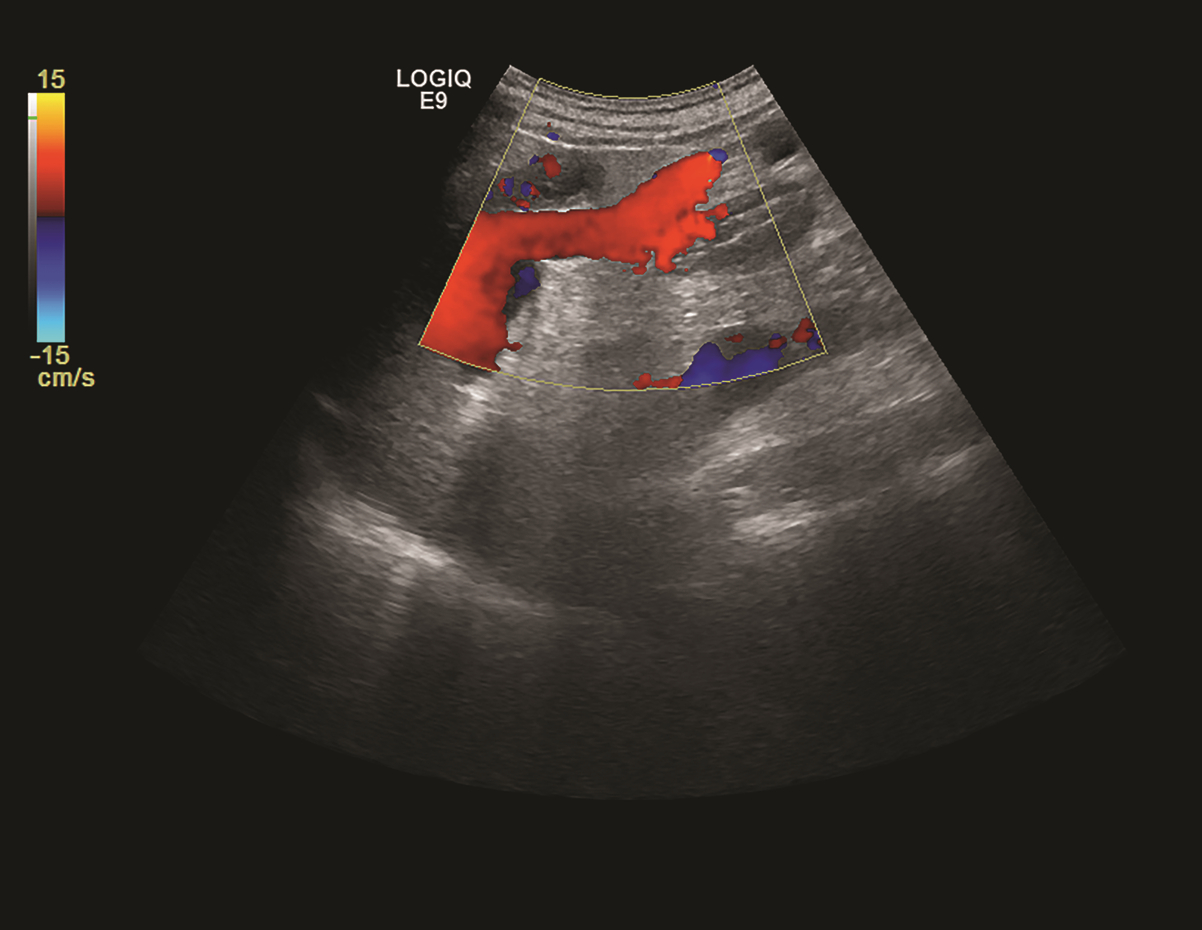

Influence of patent paraumbilical vein on the development of esophageal varices and esophageal variceal bleeding in liver cirrhosis: A protective factor or a risk factor?

Zhipeng CHEN, Fang YIN

2022, 38(4): 918-922. DOI: 10.3969/j.issn.1001-5256.2022.04.036

Abstract(2505) HTML (971) PDF (2602KB)(82)

Abstract:

Previous studies believe that patent paraumbilical vein in cirrhotic portal hypertension can reduce portal venous flow, portal venous pressure, and the development of esophageal varices and esophageal variceal bleeding, but there are still controversies over this issue in clinical practice. This article reviews the formation of portal systemic collateral circulation, the characteristics of the paraumbilical vein, the definition and diagnosis of patent paraumbilical vein, and the influence of patent paraumbilical vein on the development of esophageal varices and esophageal variceal bleeding, and it is believed that patent paraumbilical vein may not reduce the development of esophageal varices and esophageal variceal bleeding. Contrary to the previous points of view, patent paraumbilical vein should be regarded as a manifestation of the progression of cirrhotic portal hypertension, which can lead to the complications such as hepatic encephalopathy, and therefore, targeted prevention measures should be adopted in clinical practice.